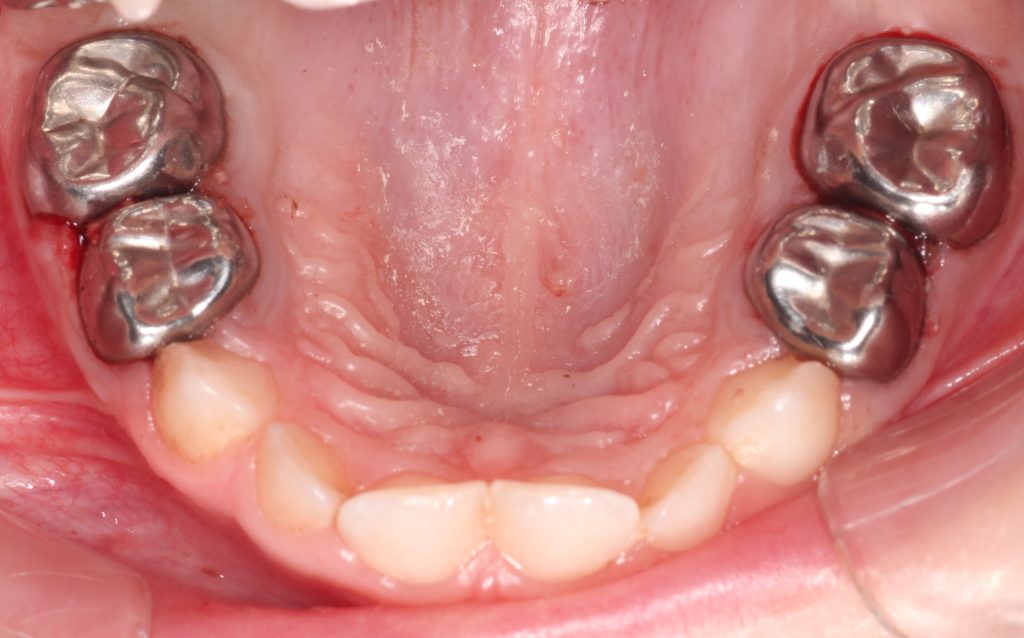

Özellikle genel anestezi altında diş tedavisi yapmayı planladığımız hastalarımızda tedavi planlarken, dişin düşmesine ne kadar süre kaldığı bizim için çok önemli bir faktör. Burada bu tatlı kız çocuğu 5 yaşında ve ikinci süt azısının düşmesine 7 yıl, birinci süt azısının düşmesine 4 yıl var. Bu süre içerisinde çocuğun dişinin, dolgu olmayan diş yüzeylerinden tekrar çürümesini istemeyiz. Çünkü böyle bir durumda, çocuğunuz tekrar koltukta işlem yaptırmayabilir, yine korkabilir ve yeniden genel anestezi altında diş tedavisine ihtiyaç duyulabilir. Böyle bir durumla karşılaşmamak için, bizim için pedodontide altın standart olan, kızlar için “simli diş” erkekler için “demir adam” dişi dediğimiz paslanmaz çelik kaplamalar imdadımıza yetişiyor. Böylelikle çocuğunuzun dişlerinin diğer yüzeylerden çürümesinin de önüne geçmiş oluyoruz. Bu vakada da böyle yaptık. Okuduğunuz için teşekkürler.